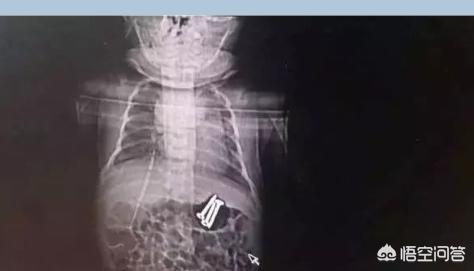

6月5日21:00左右,一条微信在河南医务人员朋友圈热传:“杀手”无处不在,危险此起彼伏。二孩时代,熊孩子无所不能,这个3岁哥哥喂给37天弟弟的三枚3.5厘米的螺丝钉,经我们消化科同仁成功取出。

看了这,真是替那个小宝捏把汗,得亏最后通过胃镜把三枚钉子取出来了,钉子也没伤到孩子的食管。真是不幸中的万幸啊!有惊无险。